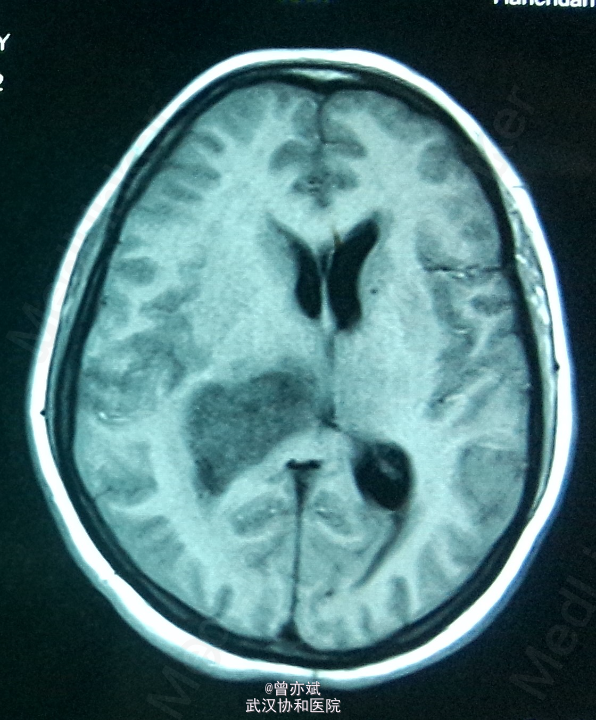

侧脑室占位一例

主诉:间歇性头痛半年余,加重一月 简要现病史:患者半年前无明显诱因出现间歇性头痛,无发热、恶心呕吐、肢体无力、抽搐等症状,近一月来,头痛症状加重,当地医院行MRI提示侧脑室占位。

专科查体神志清楚,双侧瞳孔等大等圆,直径约3mm,光反射灵敏,四肢肌力4级,生理反射村子啊,病理反射未引出。 MRI提示右侧 脑室巨大占位

诊断:右侧侧脑室占位:室管膜瘤? 处理:手术治疗